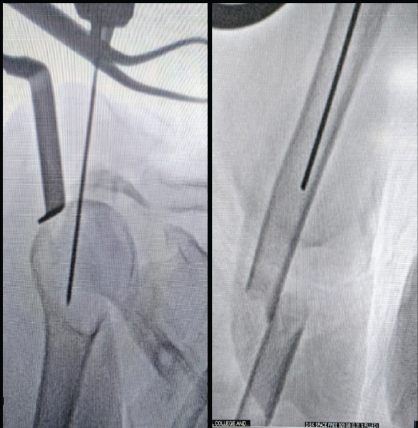

The patient in beach-chair positioned on a radiolucent table with a small bolster beneath the scapula to extend the shoulder. Through a 3 cm anterolateral incision, the deltoid was gently split and the cuff divided in line with its fibers. The entry point was made at the apex of the humeral head just medial to the greater tuberosity, under fluoroscopic control (Fig. 2).

Figure 2: Entry was made at the apex of the humeral head just medial to the

greater tuberosity.